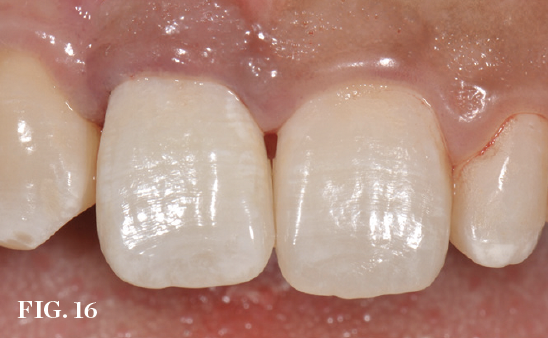

(16.) Postoperative view after immediate implant placement and provisional restoration on the day of surgery.

Figure 16